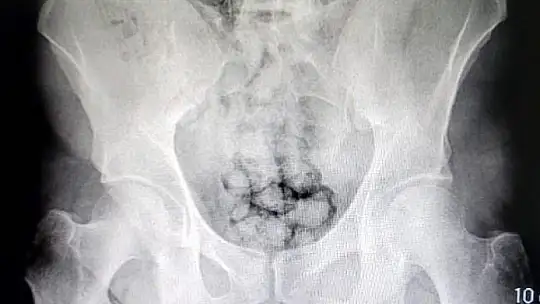

Kayseri İl Emniyet Müdürlüğü Narkotik Suçlarla Mücadele Şube Müdürlüğü ekipleri uyuşturucu madde ticareti yapan iki yabancı uyruklu şahsı takibe aldı. Ekipler, hareketlerinden ve mide bulantılarından şüphelendiği şahısları hastaneye götürdü. Burada röntgen çekinen şahısların midesinde farklı maddeler tespit edildi. Yapılan tıbbi müdahalede şahısların midelerinde sakladıkları 70 tane kapsül haline getirilmiş toplamda 500 gram metamfetamin maddesi çıkarıldı.